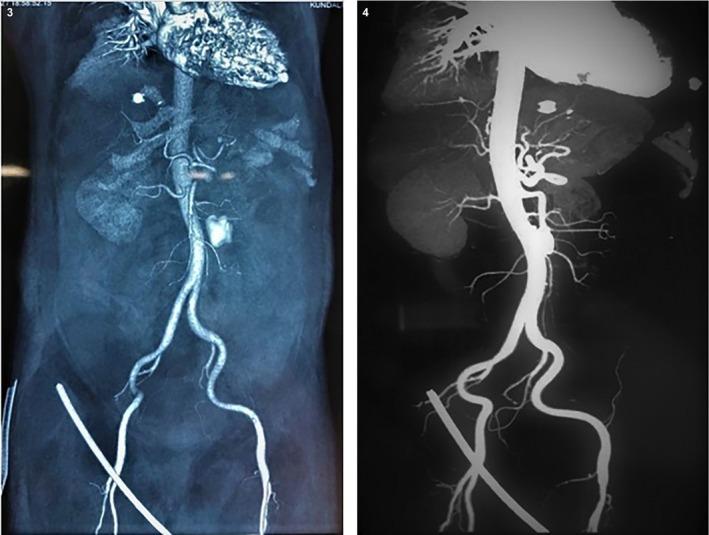

Acute splenic hematoma: A rare complication of snake bite.

Splenic hematoma secondary to snake bite is a potential complication due to snake envenomation and poses a significant risk to the health of the patients. Although relatively rare, this complication once diagnosed, should be initiated with timely anti-venom administration and supportive care. Clinicians must be aware of any signs of hematological abnormalities in snakebite patients, as the development of splenic hematoma can have serious implications for patient outcomes. Awareness of this potential complication and multidisciplinary collaboration among medical teams are crucial to ensuring effective management and optimal patient care in these clinical scenarios. Understanding this concern can improve patient prognosis and advance the overall approach to snakebite management in healthcare settings.